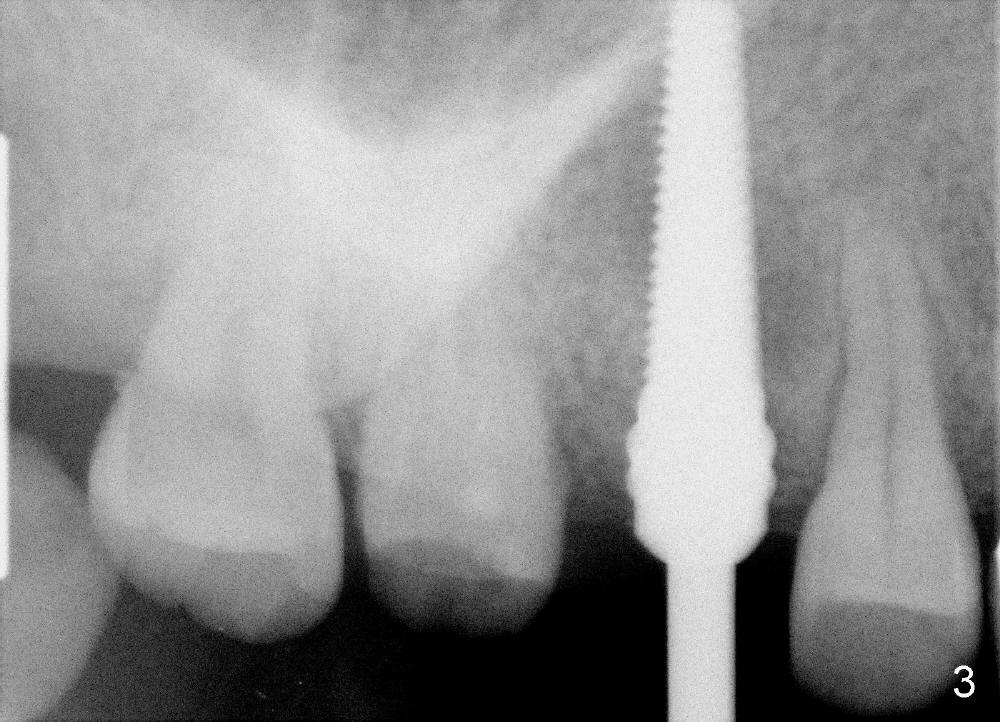

Immediate provisional is aborted due to low torque value and patient's in-cooperation (fear). A healing cuff (4.5 mm in diameter) is placed to close the buccal gap (Fig.5). The joined crowns are separated. The crown for #3 is recemented. Finally perio dressing is placed around the implant. The healing cuff is removed 6 days postop because of pressure. The patient returns for restoration 9 months postop. The gingival tissue is healthy around the implant (Fig.6). The bone density around the implant increases (Fig.7 *, compare to Fig.4).